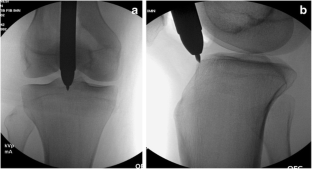

Fig. 1